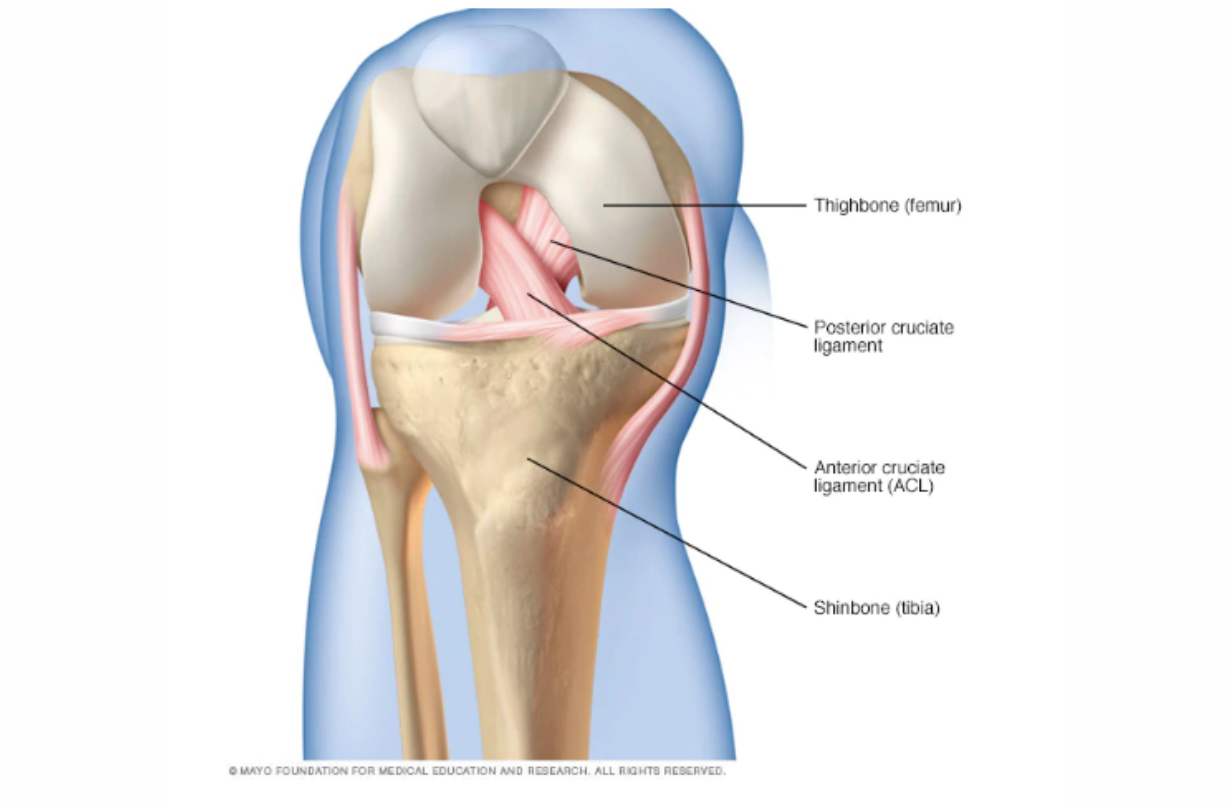

Anterior Cruciate Ligament Tear

The anterior cruciate ligament goes from the back of the femur to the front of the tibia, and keeps the shin from sliding forward.

Posterior Cruciate Ligament Tear

The posterior cruciate ligament goes from the front of the femur to the back of the tibial plateau, keeping the shin from sliding backwards. Injury often results in hyperextending the knee. BENEFICIAL POSES: Heel Sliding (see video), Janu Sirsasana, Supta Padangusthasana, Ardha Navasana, (later) Utkatasana. EXPLANATION: This uncommon injury occurs when the tibia is forced backwards, and therefore may be caused by a low tackle from the front or a fall. Treatment of most injuries is conservative: iNCREASING range of motion at the hip early, to take strain off of the knee, and strengthening later. Heel sliding maintains range of motion and coordinates ankle and hip motion with that of the knee. Strong hamstrings and quadriceps protect the healing ligament from further injury. These poses do exactly that, and should begin soon after the injury to avoid restricted range of motion later. Reference: Pierce CM1, O'Brien L, Griffin LW, Laprade RF. Posterior cruciate ligament tears: functional and postoperative rehabilitation.Knee Surg Sports Traumatol Arthrosc. 2013 May;21(5):1071-84. doi: 10.1007/s00167-012-1970-1. Epub 2012 Apr 8.